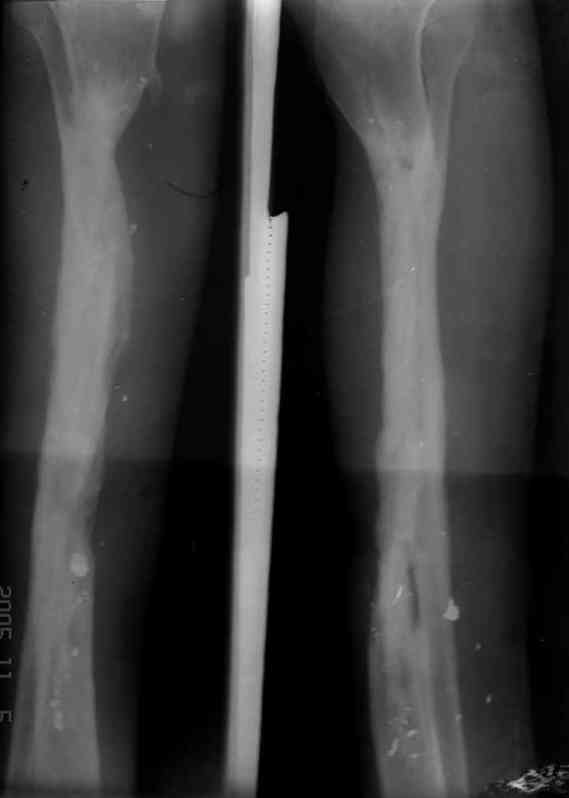

Re: case tibial defect

Я думал, что в нижнем отделе голени без мягкотканнего покрытия будет сложно проведения тибиализацию, но твой пример показывает - метод работает даже в таких трудных условиях.

Правда те мои случаи были сделаны давно, еще в Латинской Америке, и конечно качество исполнения отстает от идеалов, но, несмотря на отсутствие нормальных спиц с упором, метод сработал в свое время.

Приходилось встречать замещенные дефекты малоберцовой костью без применения метода Идизарова, и при соблюдении осторожности хрупкая малоберцовая за короткое время под вождействием нагрузки утолщались в диаметре.